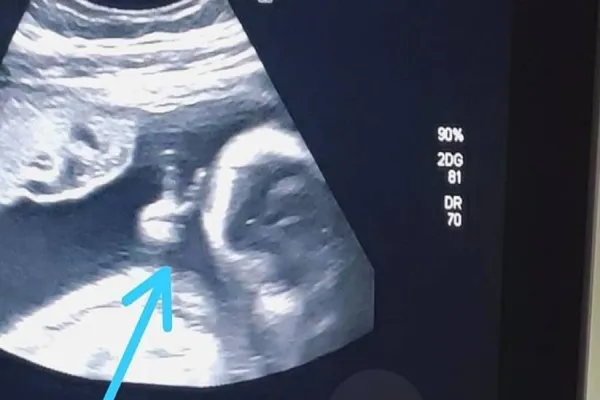

Ao acompanhar o exame de ultrassonografia de sexto mês do primeiro filho, Felipe Moreira dos Santos, de 32 anos, teve um grata surpresa: o bebê fez um ‘V de vitória’ com a mãozinha, dentro do útero. O rapaz, que é morador de Guarujá, no litoral de São Paulo, encarou como um sinal divino, já que enfrenta um câncer raro no baço

O rapaz conta que ver o ultrassom já é bem emocionante, porque consegue observar como o bebê está e ouvir seu coraçãozinho. Mas, desta vez, ele se deparou com a surpresa de ver o filho Davi fazendo um sinal de ‘V’ com uma das mãozinhas. “Até a médica falou: ‘olha, ele fez o sinalzinho de vitória com a mão’. Eu fiquei sem acreditar”, afirma. Ele encara a situação como um sinal divino de que vai conseguir superar o tratamento e vencer a doença.